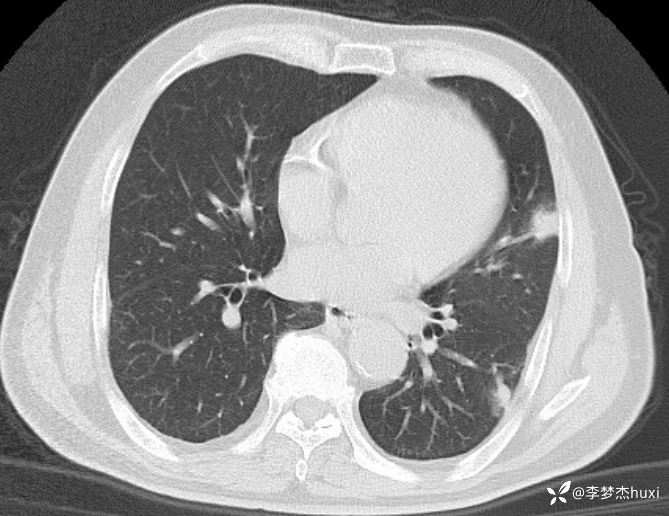

男性63岁,热伴胸痛4天,胸部CT示双肺多发结节,考虑什么疾病?

【现病史及既往史】: 1.患者老年 男,患者于入院前4天无明显诱因出现发热,具体体温不详,伴右侧胸痛,无放射痛,偶有咳嗽、无明显咳痰,无鼻塞,无咽痛,无胸闷、憋气,无恶心、呕吐,无腹痛、腹泻,无尿急、尿频、尿痛,院外口服退热药物治疗(具体不详),症状好转,今患者及家属为进一步诊治前来我院就诊,门诊查胸部CT:双肺炎症;双肺间质性改变;右肺上叶肺大疱?纵隔内肿大淋巴结,部分钙化;主动脉及冠状动脉壁钙化;双侧胸膜局部增厚;右侧第9、10肋骨欠规整?;右侧胸壁术后改变,双肺实性结节,建议复查或肺结节门诊检查,故门诊以“社区获得性肺炎,非重症”收入院。

【临床诊断】: 社区获得性肺炎,非重症。